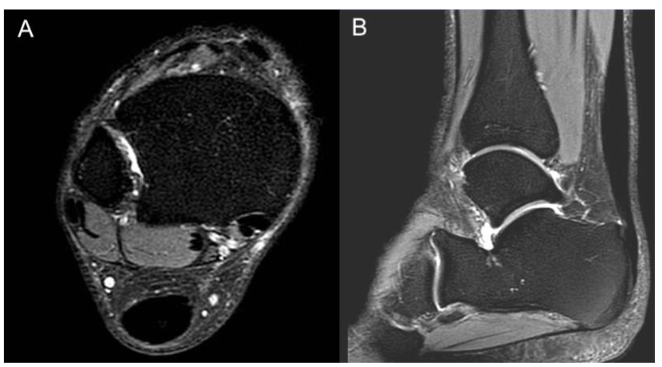

Consent was obtained for all procedures. With the patient in a prone position for the entire procedure, a US-guided popliteal block was performed with 12 ml of 1% lidocaine by the senior author (MK) for peri-procedural anesthesia. Using US guidance, a medial-to-lateral approach to the tendon was utilized to avoid the sural nerve, and a 4mm incision was made with an 11-blade in the skin at two locations along the tendon approximately 15 mm apart. Subsequently, an 18-gauge 1.5 inch needle was passed through the area of tendinosis from medial to lateral with approximately 15 passes at each incision site for initial tenotomy. The needle was withdrawn, and Tenex TX-1 needle probe (Tenex Health, Lake Forest, CA, USA) was used to debride and tenotomize the area of tendinosis with a total cut time of 150 seconds. Then, 1.5-ml Interfyl mixed with 1.5-ml normal saline was injected with US guidance into the area of tendinosis and tear. Bone marrow concentrate and platelet-rich plasma procedures were performed ten days after the tenotomy, and connective tissue matrix injection was performed to allow for the expected post-procedural edema to decrease. Each of bilateral posterior iliac crests were identified under ultrasound and anesthetized with 10ml lidocaine 1% with epinephrine, to minimize post-procedural bleeding. Then, a popliteal block, as described above, was performed. Ten minutes after periosteal lidocaine injection, an 11-gauge jamshidi was utilized to penetrate beneath the left posterior iliac crest boney cortex, and 2ml bone marrow was aspirated into a 10ml syringe preloaded with 1ml A-CDA and 0.25ml heparin 1:10,000. Jamshidi was advanced 2-5 mm deeper before another 2ml bone marrow was aspirated. This procedure was repeated until 30ml bone marrow was aspirated into three 10ml syringes, and then repeated on the contralateral posterior iliac crest. Small volumes of bone marrow were aspirated in this manner to achieve higher mesenchymal stem cell counts and lower peripheral blood contamination size. 60ml antecubital blood was aspirated with a 17-gauge needle and large-bore tubing to decrease premature platelet activation. Bone marrow and blood were centrifuged separately under leukocyte-rich protocols with an Arthrex Angel centrifuge (Arthrex, Naples, FL). Then with a 22 gauge 1 ½ inch needle and US guidance, 4ml platelet-rich plasma and 4ml bone marrow concentrate was peppered into the area of Achilles tendinosis and partial tear as shown in Figure 2.

Figure 2: Ultrasound image of the short-axis, in-plane bone marrow concentrate injection into the Achilles Tendon using a medial-to-lateral approach.